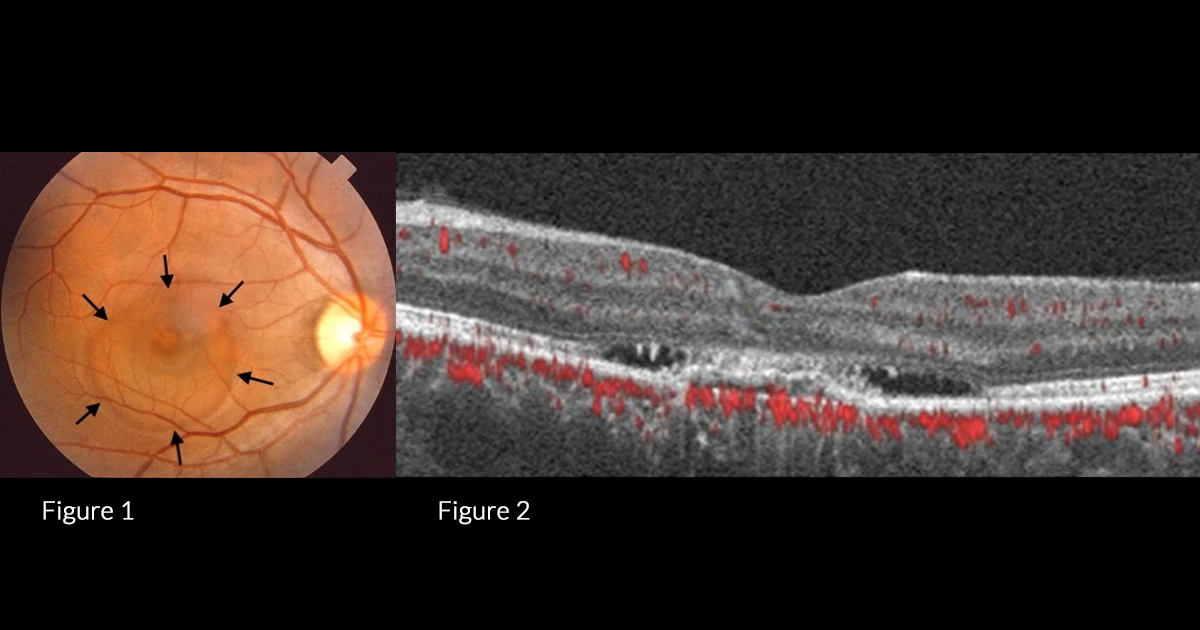

A 60-year-old caucasian male was referred with complaints of a gradual reduction in visual acuity over the last 12 months.